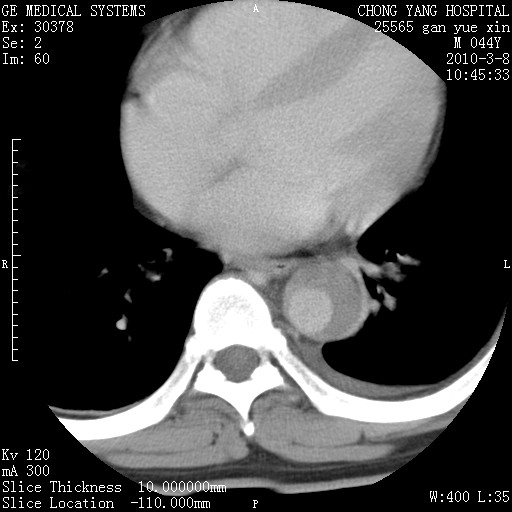

标题: CT24940:主动脉增强,典型病例。 [打印本页]

标题: CT24940:主动脉增强,典型病例。

夹层动脉瘤。

动脉夹层

夹层动脉瘤,典型

主动脉夹层。

动脉夹层的分型:

⒈debakey分型:根据主动脉夹层累及部位,分为三型:ⅰ型:原发破口位于升主动脉或主动脉弓部,夹层累及升主动脉、主动脉弓部、胸主动脉、腹主动脉大部或全部,少数可累及髂动脉。ⅱ型:原发破口位于升主动脉,夹层累及升主动脉,少数可累及部分主动脉弓。ⅲ型:原发破口位于左锁骨下动脉开口远端,根据夹层累及范围又分为ⅲa,ⅲb。ⅲa型:夹层累及胸主动脉。ⅲb型:夹层累及升主动脉、腹主动脉大部或全部。少数可累及髂动脉。

⒉stanford分型:a型:夹层累及升主动脉,无论远端范围如何。b型:夹层累及左锁骨下动脉开口以远的降主动脉。

夹层动脉瘤,少量胸水

夹层动脉瘤;左侧少量胸腔积液。

典型主动脉夹层。